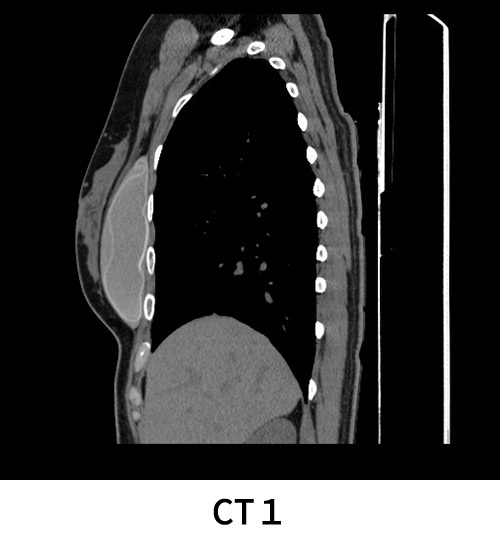

CT1

豊胸用のインプラントが長期間経過後、劣化して破損し、内部のインプラントが流出して周囲に広がっているのがCTで確認できます。周囲に感染や炎症を起こすだけでなく、シリコン以外の混入物の種類によっては様々な健康被害を起こすため、抜去が必要です。